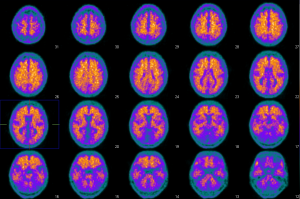

Marqueur de la Plaque Amyloïde – AV 45

Imagerie de la plaque amyloïde.

2 cas: fixation normale et fixation pathologique

Captation corticale anormale :

Captation corticale diffuse. Charge amyloïde élevée.

Mise en évidence précoce de dépôts amyloïdes, sans altération perfusionnelle